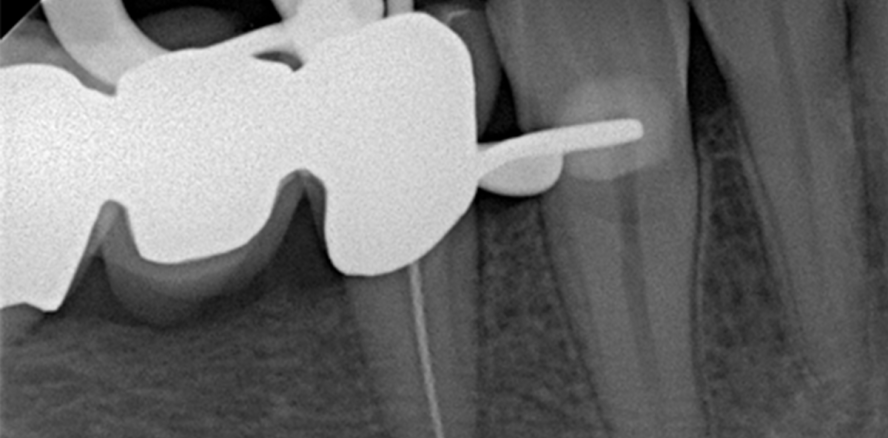

Radiologische Untersuchung

Es wurde ein Zahnfilm angefertigt. Der Röntgenbefund an Zahn 44 zeigte eine metalldichte Verschattung koronal und eine zementdichte Verschattung im Wurzelkanal, welche bis zum röntgenologischen Apex reicht. Diese erscheint im koronalen Bereich nicht randständig. Des Weiteren zeigte sich eine periapikale Aufhellung mit halbmondförmiger zementdichter Verschattung (Durchmesser ca. 2 mm), welche sich ca.1,7 mm apikal vom radiologischen Apex von Zahn 44 befindet (Abb. 1).

Als Diagnose ergab sich dental eine Situation Post-Wurzelbehandlung und parodontal eine akute apikale Parodontitis. Die vorhandene Wurzelbehandlung muss als Misserfolg bewertet werden. Grundlage sind zum einen die akuten Beschwerden des Patienten, zum anderen Hinweise in der Röntgenaufnahme, die darauf schließen lassen, dass der Wurzelkanal unterfüllt ist.